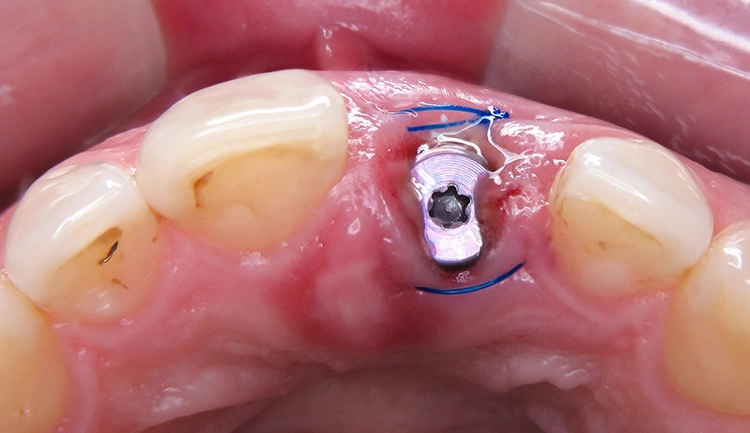

Unter Lokalanästhesie wurde der beherdete Zahn 21 extrahiert und hierbei auf die maximale Schonung der vestibulären Lamelle geachtet. Die Entzündung konnte rückstandslos entfernt werden. Die Sondierung ergab eine intakte faziale Knochenlamelle (Abb. 6). Die frische Extraktionsalveole wurde als Implantatbett aufbereitet und das Implantat (BLX ø 4 mm, 14 mm) entsprechend der Planung dreidimensional im palatinalen Bereich der Alveole inseriert [3,6] (Abb. 7 und 8).

Das BLX-Implantat hat einige Besonderheiten im Design. So nimmt beispielsweise das Gewinde des Implantats zum krestalen Bereich hin an Stärke zu, sodass zusätzlich zur horizontalen Kondensation auch vertikal Knochen kondensiert wird. Ziel ist eine Primärstabilität im gesamten Implantatbett basierend auf einer homogenen Krafteinleitung. Drucknekrosen sollen so verhindert werden. Im krestalen Bereich ist das Implantat um 1/10 reduziert, um das sensible Gewebe in der Kortikalis drucklos zu lassen. Das BLX-Implantat konnte mit einer für die Sofortversorgung ausreichenden Primärstabilität (mind. 45 N/cm2) inseriert werden.

Augmentation

Der Resorption der bukkalen Lamelle soll durch die Augmentation bestmöglich entgegengewirkt und die Knochenneubildung unterstützt werden. Erfahrungsgemäß führt das Füllen des Gaps in vielen Fällen zu einem besseren Ergebnis. Aufwendige Folgeaugmentationen lassen sich oft vermeiden. Verwendet wurde in diesem Fall ein Knochenersatzmaterial [4]. Nach dessen Einbringen und dem Aufsetzen der Abdeckschraube wurde die Situation mit einer Matratzennaht verschlossen (Abb. 15).